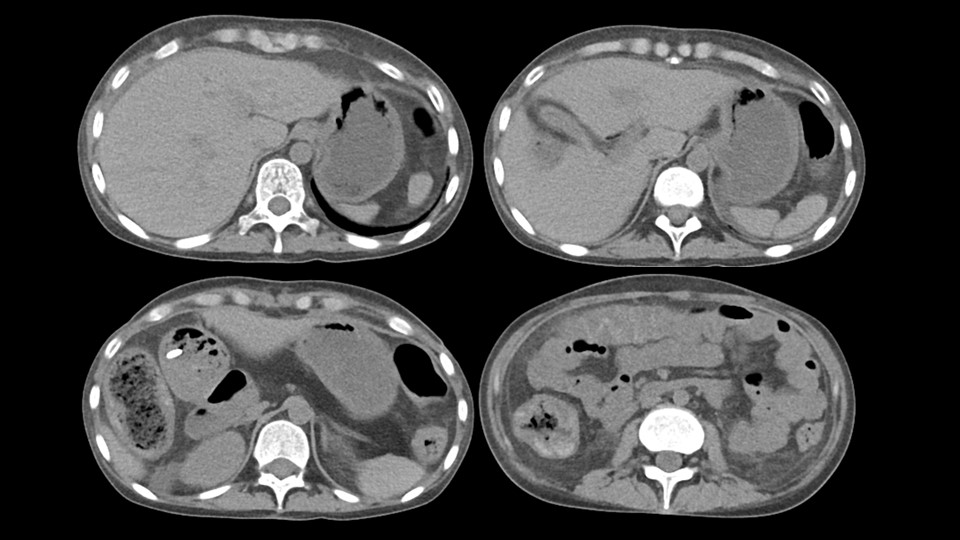

Case

No.721

F / 66

Growing splenic mass

ABDOMEN

¼¿ï¼º¸ðº´¿ø ±èÀ¯¼±

CASE2

18